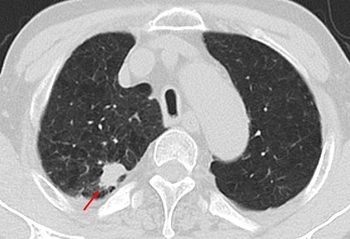

[사진 : 저선량 흉부 CT 검사에서 2.4cm 크기의 폐결절(붉은색 화살표)이 확인됐고, 추적관찰 결과 폐암으로 진단됨]

양성 폐결절은 암(악성)이 아니지만 극히 일부는 폐암으로 진단되거나 크기가 증가하며 폐암으로 진행될 수 있어서 추적관찰이 요구된다. 양성 폐결절 환자에게 적절한 추적관찰을 진행한 결과 2.2%(31명)가 폐암으로 진단됐다.